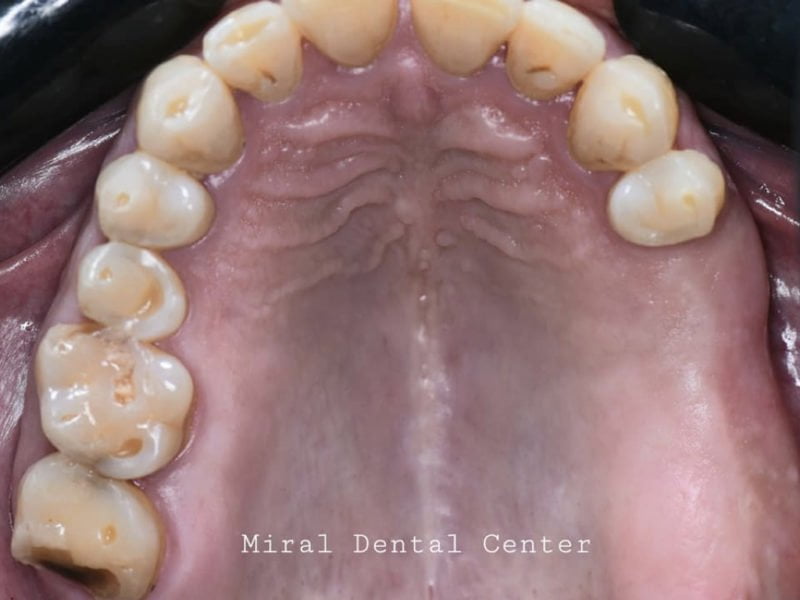

In this case we used the implant cap to model the peek healing screw and obtain a different gingival profile more suitable for the implant site.